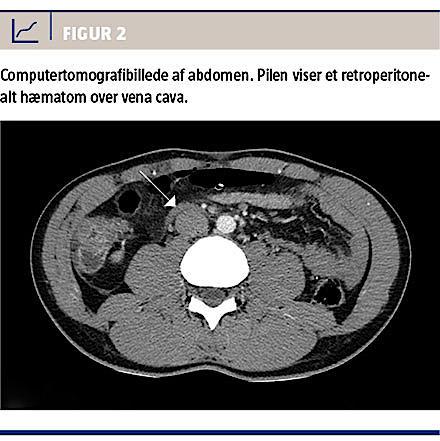

Efter operationen blev der foretaget akut computertomografi af abdomen med intravenøs kontrast for at visualisere størrelse og evt. progression af hæmatomet. Skanningen viste en lille ansamling på 6 mm

beliggende lige foran vena cava inferior på L3/L4-niveau (Figur 2). Efter konference med Karkirurgisk Afdeling på Odense Universitetshospital blev der ikke foretaget yderligere diagnostik eller behandling. Patienten forblev indlagt til tæt observation og blev udskrevet i velbefindende dagen efter.